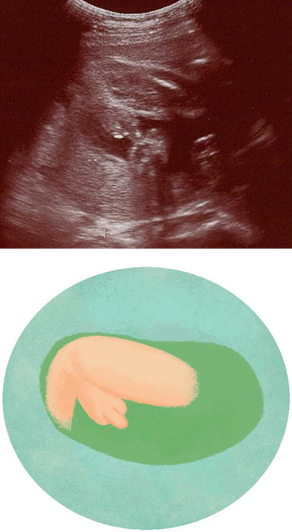

妊娠26週ころの超音波写真

男の子のシンボルが写ることもあります

性器が見えて、赤ちゃんの性別がわかることも。このころは、推定体重や部位のバランス、赤ちゃんの動きから、発育や元気さをチェック。羊水量が正常な範囲かも確認されます。